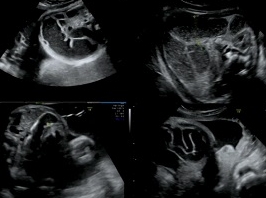

Mobilité orale, digestive et trachéale

• Date : 20/06/2013